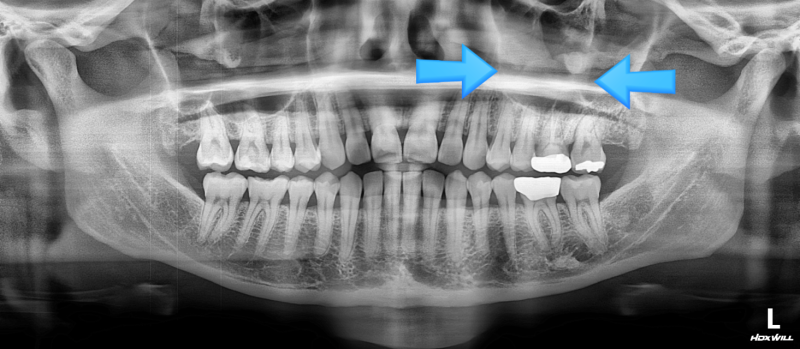

교정치료 중인데 어금니 농낭이 생겨서 계속 재발해서 치료를 위해 의뢰해 주셨습니다. 기존에 신경 치료나 재신경 치료 후에도 병소가 계속 재발하고 있습니다. 1. 왼쪽 아래 어금니 잇몸 농포 2. 기존 신경치료는 잘 되어 있다(<-신경치료/재신경치료 후에도 병소가 계속 재발한다) 3. 걱정치근 쪽에 병소가 생기는 교정치료는 6개월 이상 남아 있어 발치를 원치 않는 상황이었습니다.

농낭의 명확한 원인을 파악하기 위해 gp컨트레이싱을 합니다.확실히 걱정되는 치근 쪽에 들어 있는 것이 확인됩니다.